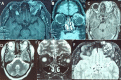

Masson tumor is a benign vascular lesion characterized by an intravascular papillary endothelial hyperplasia. Peri orbital locations are rare. We report a case of Masson tumor localized in the upper internal angle of the left orbit revealed by progressive ocular proptosis. Orbital computed tomography (CT) scan and magnetic resonance imaging (MRI) showed a vascular mass in the left internal canthus mimicking an arterioveinous malformation. The patient underwent total removal of the lesion with a favorable postoperative follow up. Histological examination found an intravascular papillary endothelial hyperplasia without atypical features corresponding to Masson tumor. A thorough literature review of Masson tumor is presented with a discussion of clinical findings and management.